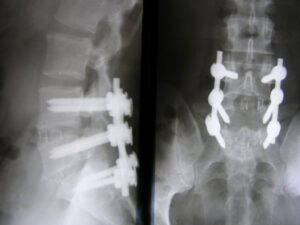

Stabilisierungsoperationen (Spondylodese, Fixateur interne) bei degenerativen Veränderungen und nach Traumata der LWS

Mit zunehmendem Alter kommt es durch Alterungsprozesse bei relativ vielen Menschen nicht nur zu Verengungen des Wirbelkanals, sondern auch zu Instabilitäten (sog. Gleitwirbel (Spondylolisthesis)) oder Skoliosen (S‑förmige Krümmung der Wirbelsäule). In bestimmten Fällen führt dies zu heftigen Schmerzen im Rücken und/oder in den Beinen, so dass die Gehstrecke immer weiter reduziert wird.

Diese Instabilitäten können zu einer Zunahme von Verengungen des Wirbelkanals (Spinalstenose) oder der Austrittslöcher von Nervenwurzeln (Foramenstenosen) führen.

Bei hohem Leidensdruck empfiehlt sich schließlich eine Operation. Das Wirbelgleiten ist dabei nur durch eine aufwendige Operation zu therapieren, bei der die Wirbel mit einem Schrauben-Stab-System (Fixateur interne) miteinander fixiert werden. Der Bandscheibenraum wird zusätzlich ein- oder beidseitig ausgeräumt und mit Knochen und einem Platzhalter (Cage) mit dem Ziel gefüllt, dass die Wirbel im Verlauf knöchern verschmelzen (Fusion). Teilweise ist eine spätere Entfernung der Implantate bei einfacheren Traumata und sicheren Fusionen denkbar.

Auch bei sich wiederholenden Bandscheibenvorfällen in der gleichen Bandscheibenetage können Stabilisierungsoperationen zur Vermeidung rezidivierender Bandscheibenvorfälle angezeigt sein.

Für Frakturen der LWS und BWS sind Stabilisierungsoperationen ebenfalls häufig erforderlich.

Stabilisierungs-Operationen können offen chirurgisch oder minimal-invasiv durchgeführt werden. Die Methoden richten sich nach der Komplexität der krankhaften Wirbelveränderungen. Unabhängig von der Technik ist auch bei mehrstündigen Operationen nur selten eine Bluttransfusion erforderlich. Die erste Mobilisierung des Patienten kann schon am Folgetag der Operation erfolgen. Die Gabe von Schmerzmitteln ist individuell verschieden und muss der Situation angepasst werden. In der Regel können Patienten nach einer solchen Operation nach fünf bis acht Tagen das Krankenhaus verlassen und wieder in die häusliche Umgebung zurückkehren. Eine Rehabilitation sollte hier frühestens nach sechs Wochen begonnen werden, um die innere Stabilisierung nicht zu früh und zu intensiv zu beanspruchen.

Bilder:

MRT: Wirbelgleiten LW4/5 mit absoluter Spinalstenose

Die Erfolgsrate der Stabilisierungsoperationen hängt sehr von den vorbestehenden Beschwerden, der Ausprägung des Befundes und der beruflichen Belastung ab. Leichte körperliche Tätigkeiten sind i. d. R. wieder nach drei bis sechs Monaten möglich.